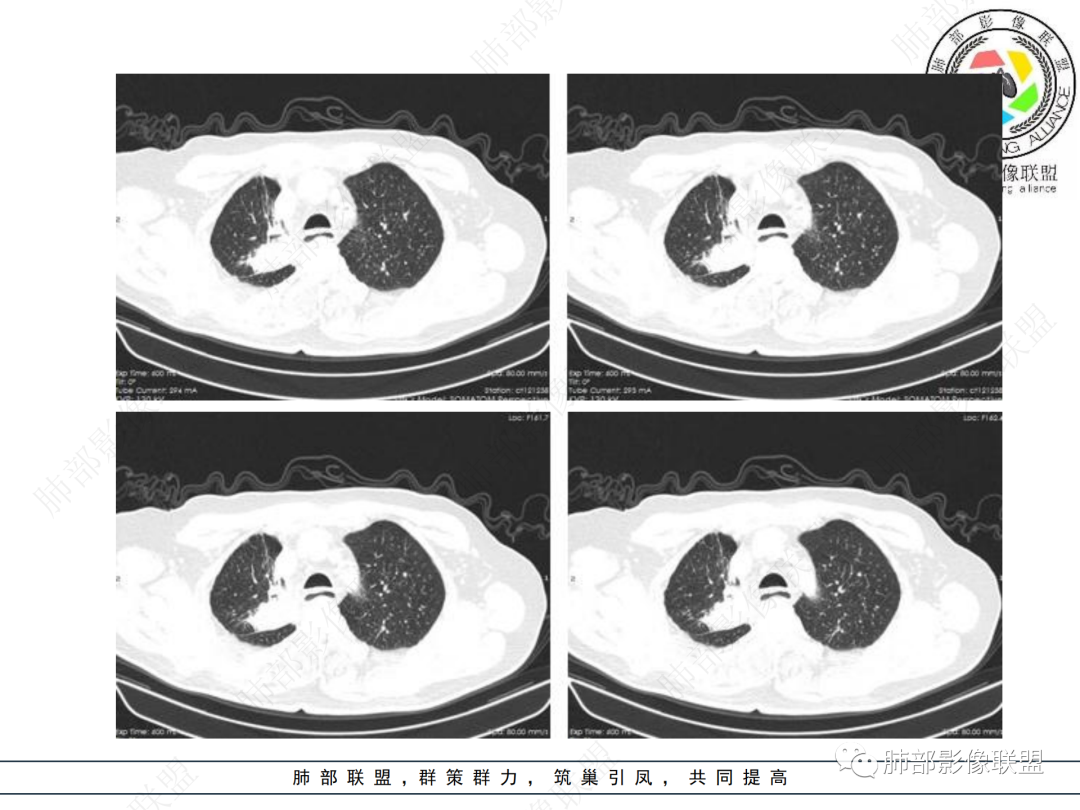

右肺上叶体积变小,见不规则实性病灶,边缘有平直,长软毛刺,邻近胸膜明显增厚,叶间胸膜牵拉上提、局部凹陷;病灶周围不干净,可见长索条影;近端支气管壁略增厚。增强后增强不均匀,有低密度坏死,间隔较厚。考虑慢性炎性肉芽肿,结核可能,鉴别腺癌。

右肺上叶尖后段不规则斑块病灶,后缘以斜裂为界,有边缘平直,周围见纤维及多发小卫星灶,邻近胸膜反应性增厚,纵隔胸膜下少量积液,同时右肺中叶内侧段支气管扭曲及牵引性扩张,周边见爬行征,胸廊入口变窄,纵隔未见淋巴结肿大,综合上述慢性炎性肉芽肿,结核可能性大,支气管镜肺泡灌洗!

结合本病例,老年男性患者,慢性病程,急性加重,无吸烟史,影像学表现为右肺上叶尖后段斑片实变密度影,整体边界清晰,边缘平直收缩为主,周边散在纤维条索影,内部见支气管内粘液栓,血管影走形正常,没有明显破坏,增强扫描明显强化,缺乏典型分叶毛刺、胸膜改变,病灶也未显示清楚的磨玻璃勾边,病灶大而肺门纵隔未见肿大淋巴结,综合考虑慢性炎性肉芽肿可能性大。但恶性,结核能完全排除吗?我想对临床医生来说还是有很大考验的。